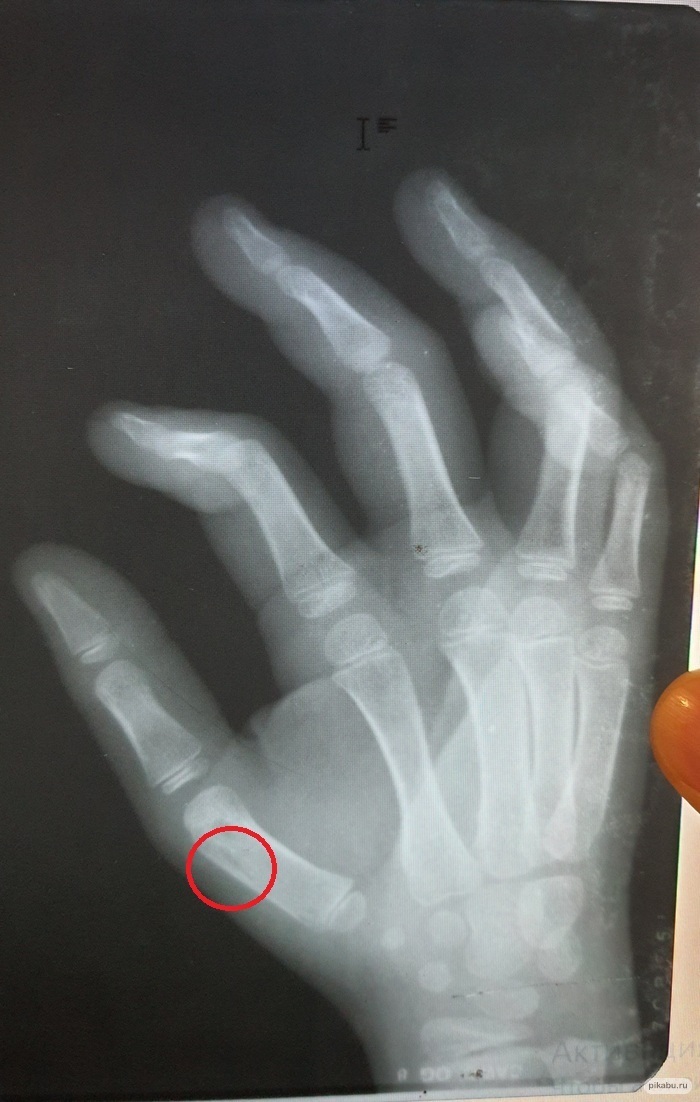

Ты молодой так как зоны роста ещё открыты.

Есть такие переломы.... эпифизиолиз. Линия перелома проходит по зоне роста костей. Если нет смещения то трудно по рентгенграмме поставить такой диагноз.

Локализованная боль, боль при осевой нагрузке, отёк локальный, характер развития боли (на момент травмы он наиболее выражен а при ушибе и растяжении боль усиливается по мере развития отёка), крепитация (ооочень редко). То ставят предварительный диагноз эпифизиолиз с указанием локализации, накладывают гипсовую лонгету и отпускают на 10-14 дней. При повторном рентгенографии смотрят... нет ли костной мозоли. Если есть, то укрепляют лонгету и назначают гипсовое лечени на длительность в зависимости от локализации перелома. Если нет костной мозоли... снимают лонгету и отправляют гулять на все 4 стороны.

Резюме: снимки не очень хорошего качества, нерезкие; но переломов я на них не вижу.